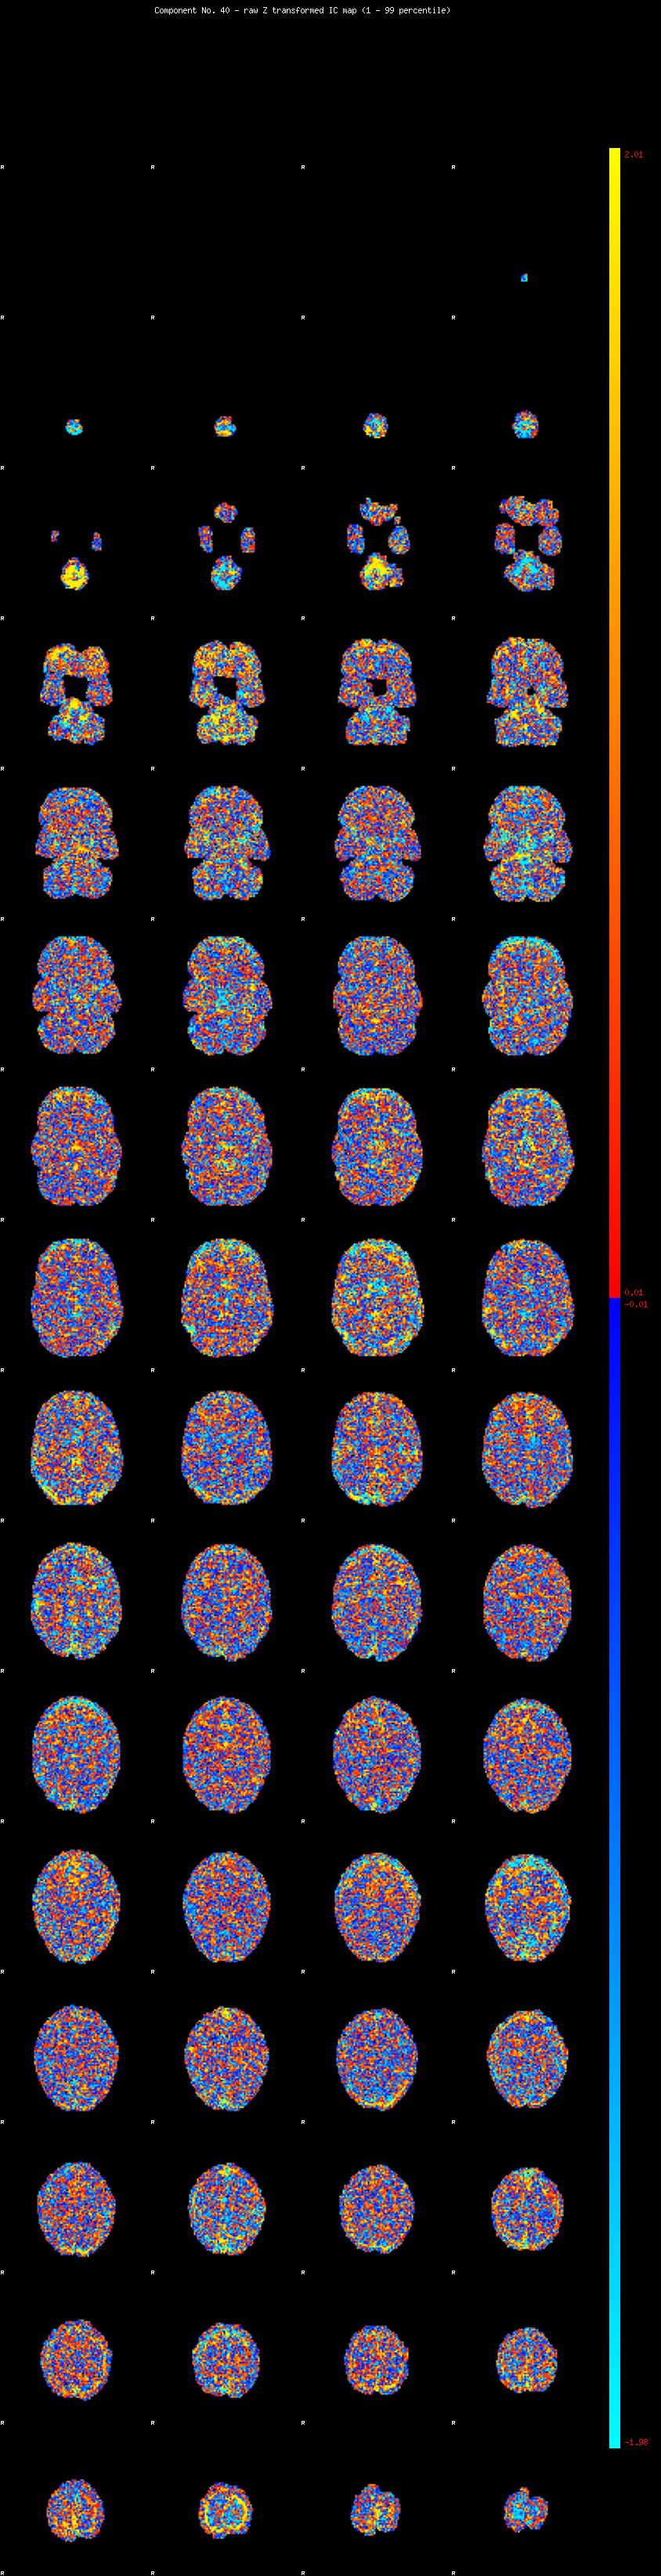

IC_40 Mixture Model fit

Means : 0.000000 2.615925 -2.376638

Vars : 1.000000 2.475756 1.694446

Prop. : 0.934298 0.032385 0.033316